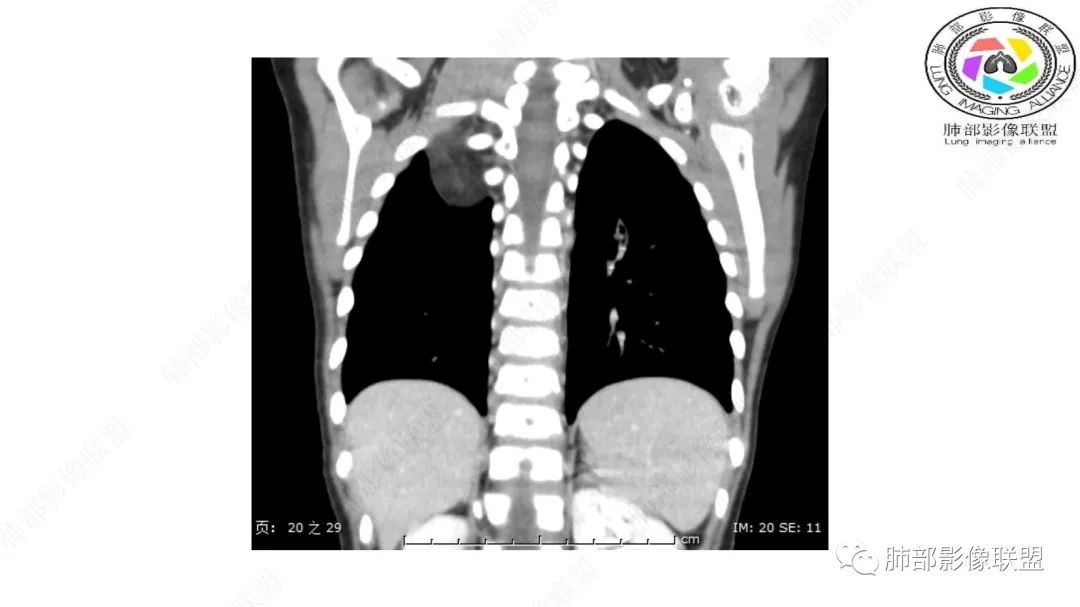

手术记录:见右肺上叶肿物,肿物与右肺上叶关系密切。与纵隔无粘连,逐步分离肿物,见肿物大小约6cm*5cm,边界清楚,于右肺上叶粘连,边界清楚,肿物包绕右肺上叶血管及支气管。超声刀逐步游离肿物,完整切除肿物,右肺上叶肺组织无破溃,表面无出血。

1.右上肺-纵隔交界区巨块影,主体位于右肺一侧,紧贴胸腺、头臂干、右锁骨下动脉、上腔静脉、奇静脉等,不能分离,但病灶整体边界清楚。注意上述相邻腔静脉等结构未见受压变形,纵隔亦未见明显向左推移,至少提示两点:

2.肺动脉穿行也许是肺内来源最重要支持点!